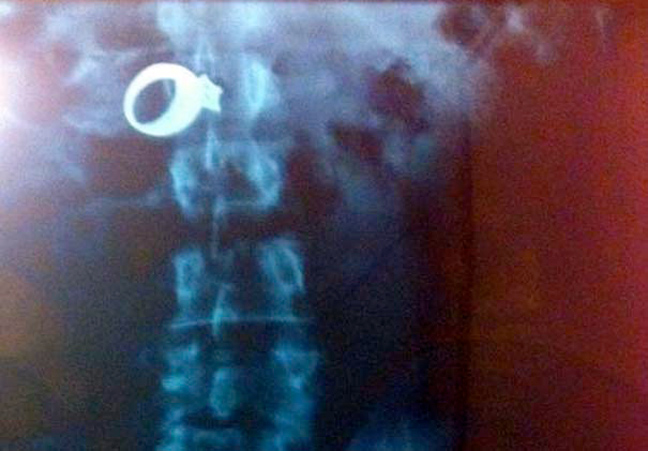

Δαχτυλίδι αρραβώνων Κλειδί Κουζινικά Χελι Μαγνητάκια Καρφιά 78 Κουτάλια και πιρούνια Φίδι

Ο,ΤΙ ΝΑ 'ΝΑΙ #φωτογραφίες Όταν μιλούν οι ακτινογραφίες! Αντικείμενα -και όχι μόνο- μέσα σε ανθρώπινα σώματα… 24·09·2013 13:33 16 σχόλια Δαχτυλίδι αρραβώνων Κλειδί Κουζινικά Χελι Μαγνητάκια Καρφιά 78 Κουτάλια και πιρούνια Φίδι